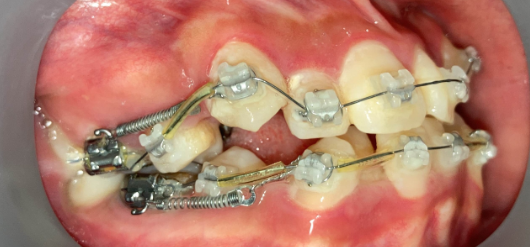

インプラントアンカー(矯正用ネジ)の口腔内写真|奈良の矯正歯科

インプラントアンカー装着中の矯正治療経過|奈良の矯正歯科

アンカー装着中

インプラントアンカーで上の歯列全体を後方に移動。抜歯せずにガタガタと口元の突出感を改善しました。

ℹ️ ただし、この方法には限界があります。歯を後ろに動かせる量には上限があるため、口元の突出が大きい場合やガタガタが重度の場合は、非抜歯では対応できません。適応かどうかは精密検査で判断します。